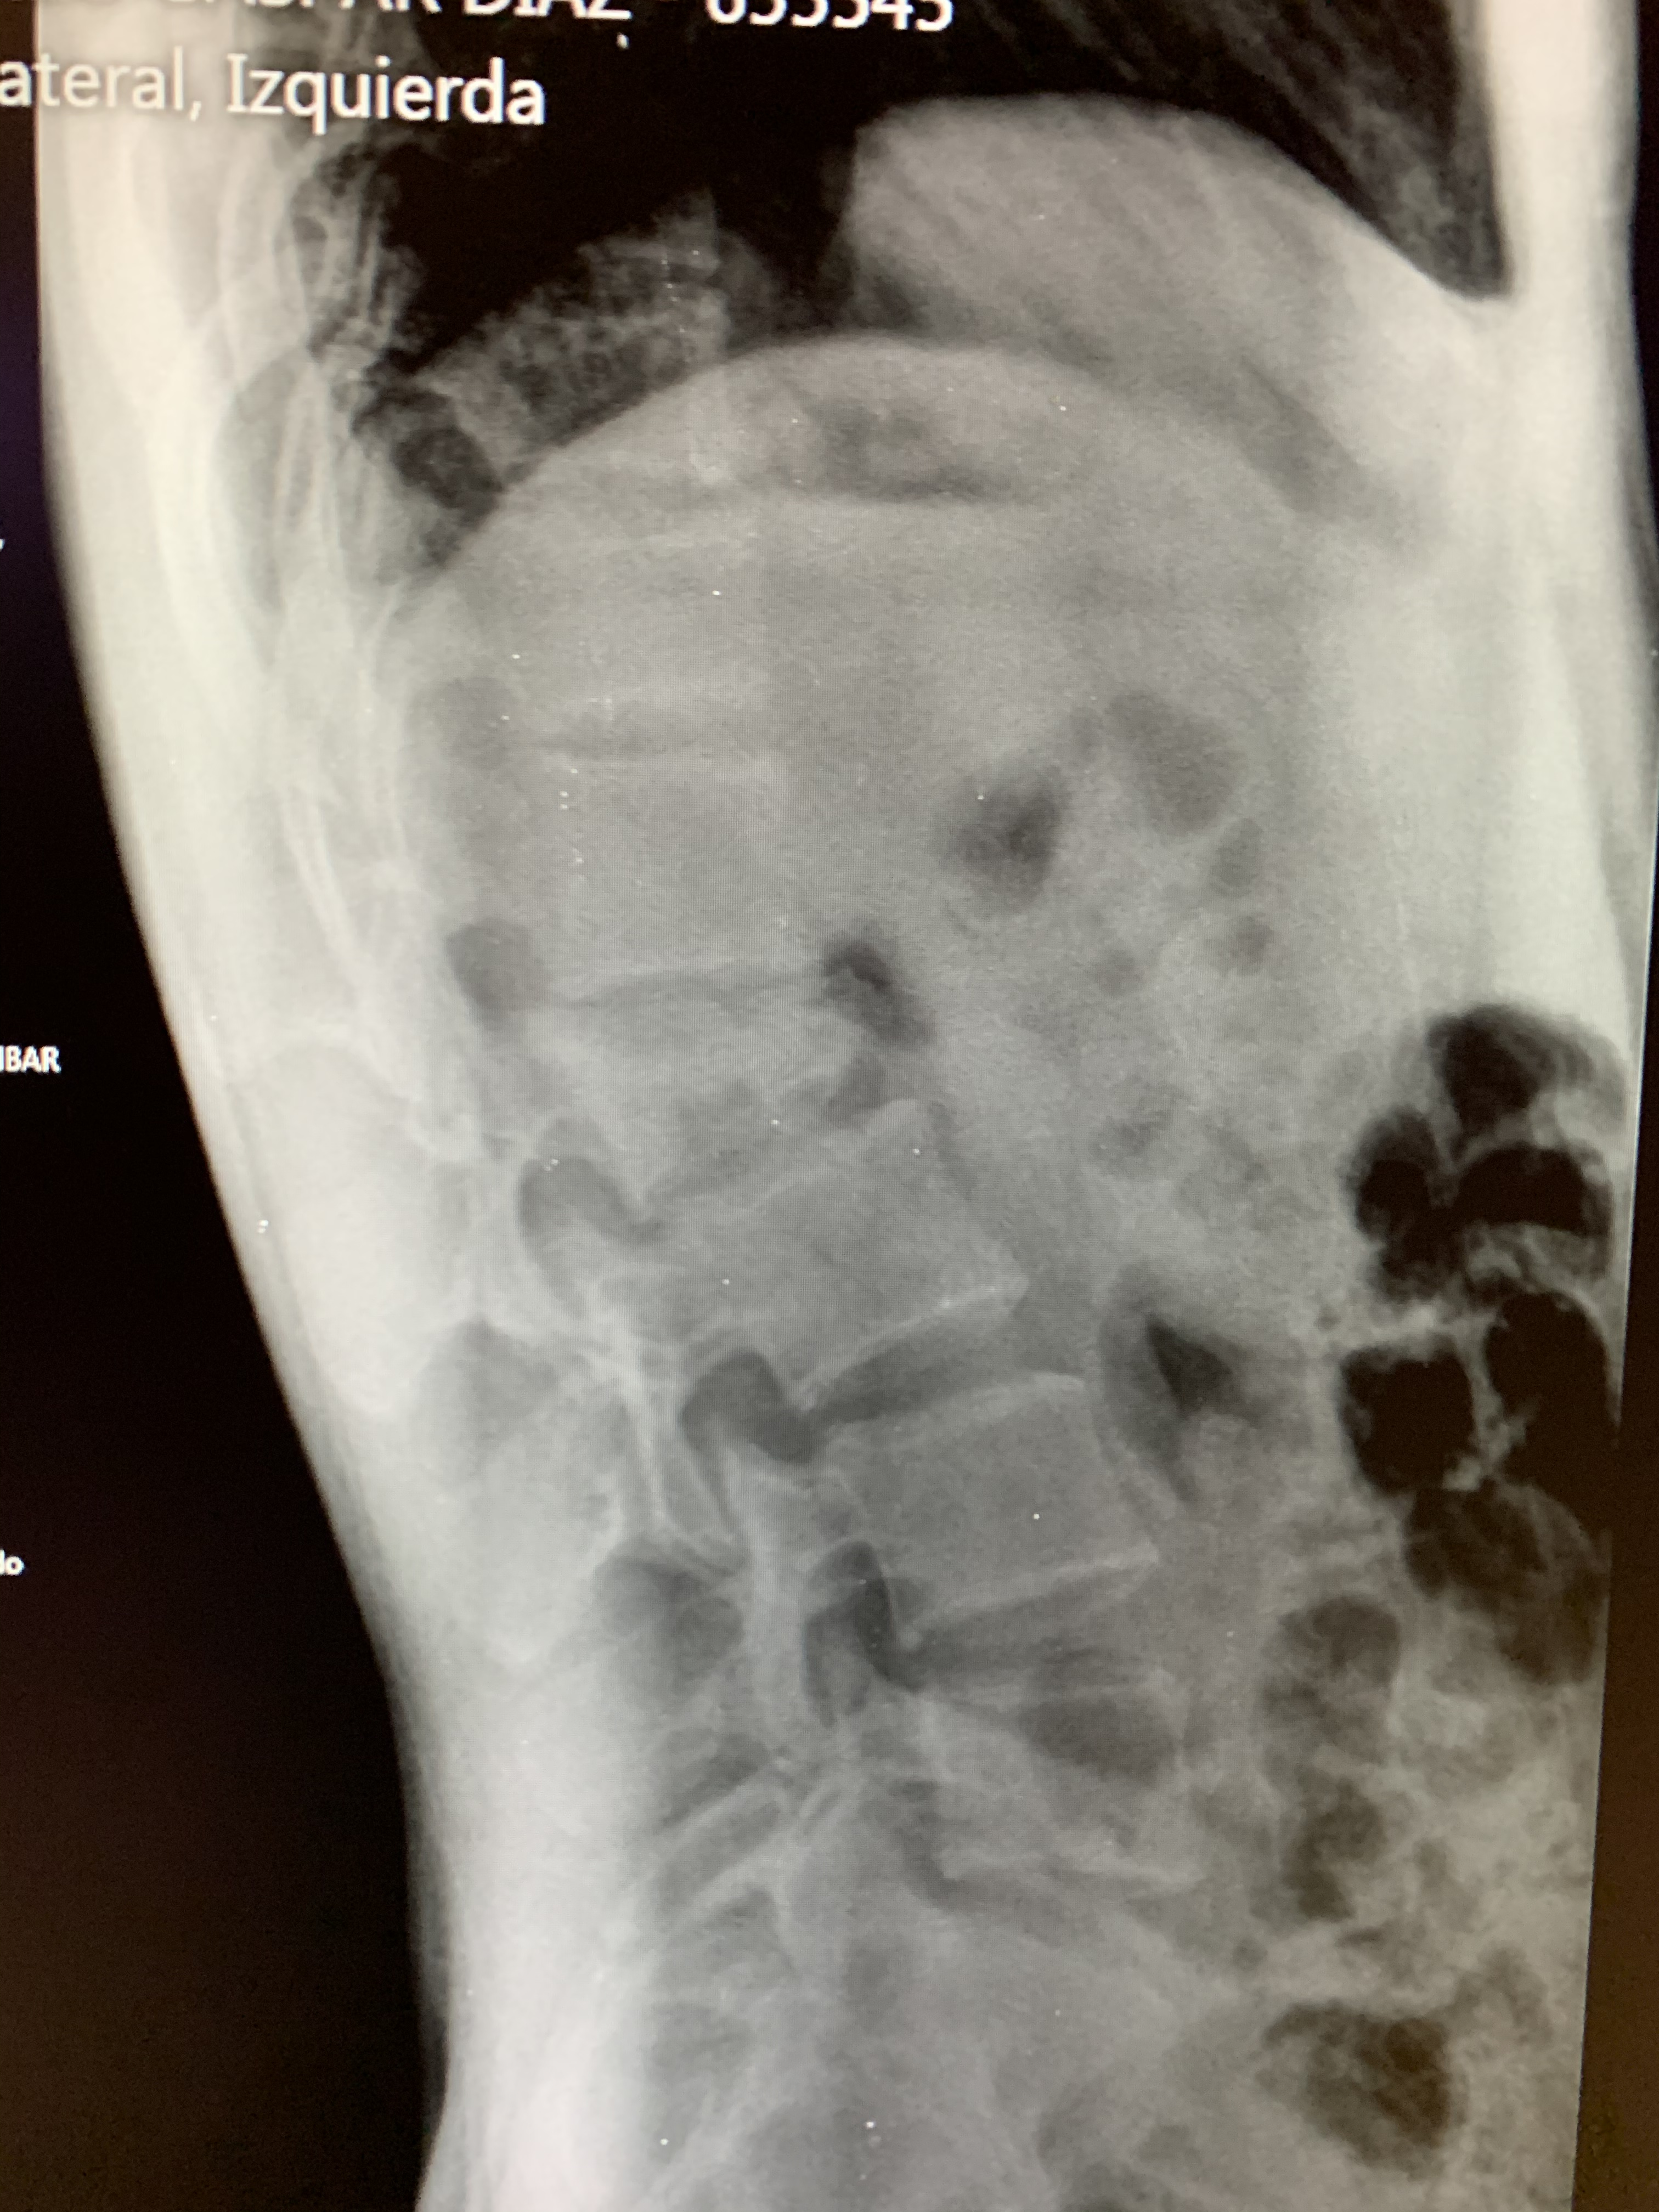

Galería de fotos clínica, servicios, cirugías, casos de pacientes Visítenos, ambiente limpio, agradable y seguro. Trabajando Operando en tiempos de coronavirus Dr Barquero Traumatologo Compartir en X (Se abre en una ventana nueva) X Comparte en Facebook (Se abre en una ventana nueva) Facebook Imprimir (Se abre en una ventana nueva) Imprimir Compartir en WhatsApp (Se abre en una ventana nueva) WhatsApp Enviar un enlace a un amigo por correo electrónico (Se abre en una ventana nueva) Correo electrónico Me gusta Cargando...